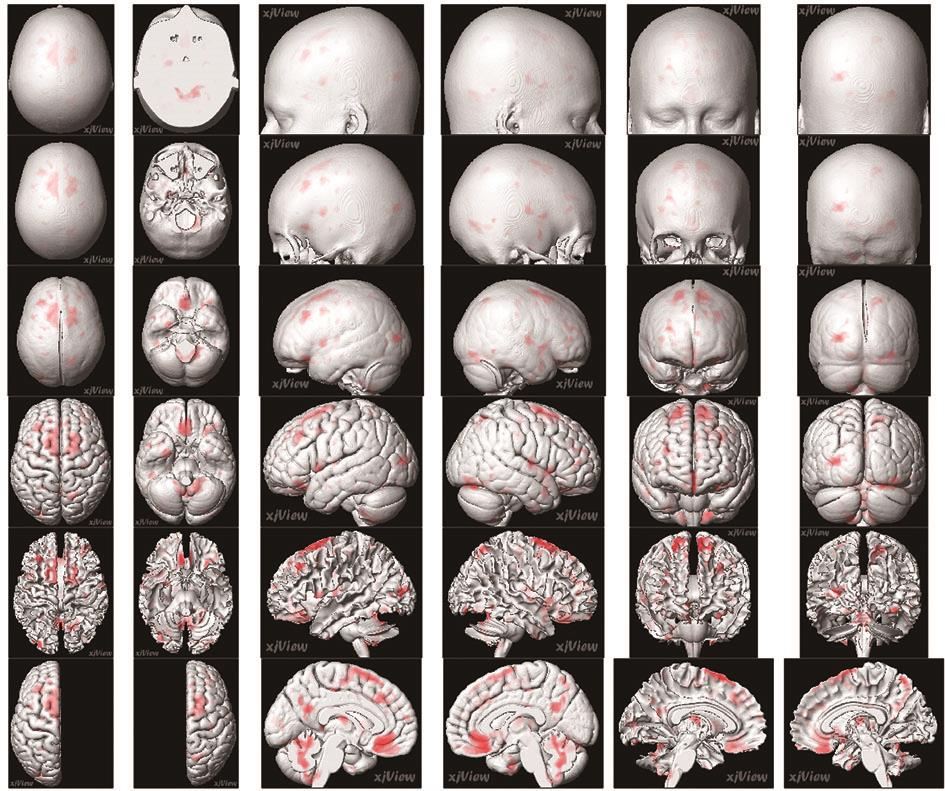

• 正常成人与伴吞咽障碍的急性脑梗死患者吞咽相关脑功能区激活机制的血氧水平依赖功能磁共振研究

2022, 47(7):802-810. DOI: DOI:10.13406/j.cnki.cyxb.003057

摘要:目的 运用血氧水平依赖功能磁共振(blood oxygenation level dependent-functional magnetic resonance imaging,BOLD-fMRI)技术对伴吞咽功能障碍的急性脑梗死患者和正常成人在吞咽活动时相应的脑功能区域激活特点进行研究,探索急性脑梗死患者吞咽功能障碍恢复过程中相关的脑功能区域调控方式。方法 选取2018年7月至2021年7月在昆明医科大学附属延安医院住院的伴吞咽障碍的急性脑梗死患者150例和正常成人100例,对其进行BOLD-fMRI扫描,记录两者在吞咽活动时相关脑功能区域的激活体积和强度,并对比两者间的差异。结果 共收集病例组150例,其中右侧脑梗死组患者50例,男29例,女21例,平均年龄(56.22±7.33)岁;左侧脑梗死组患者100例,男61例,女39例,平均年龄(58.07±6.84)岁;对照组100例,男57例,女43例,平均年龄(53.56±11.41)岁。对照组吞咽活动时激活的相关脑功能区域特点显示:两侧初级运动皮层中枢(BA4区)、运动前区/辅助运动区(BA6/8区)、缘上回(BA40区)、岛叶(BA13区)、颞上回(BA22区)、扣带回皮层(BA24区)、额叶内侧面(BA32区)、延髓、脑桥、基底核团、丘脑、小脑及左侧颞极(BA38区)和右侧颞横回(BA41区)等脑功能区激活体积和强度增加,左侧BA4区、BA40区、小脑激活体积较右侧大,差异有统计学意义(P<0.05);左右两侧脑区的激活强度差异无统计学意义(P>0.05)。右侧脑梗死病例组患者BOLD-fMRI扫描各脑区激活体积显示:右侧BA4区、BA6/8区激活体积较对照组减小,左侧BA6/8区、BA4区激活体积较对照组增大,双侧后扣带回皮层的BA23和顶叶内侧面BA31区体积较对照组增大,左侧视觉中枢的BA18/19和BA41区皮层激活体积较对照组增大,差异有统计学意义。右侧BA4区、BA6/8区、BA40区、BA13区激活强度较对照组降低,差异有统计学意义。左侧脑梗死病例组患者BOLD-fMRI扫描各脑区激活体积显示:左侧BA4区、BA6/8区的激活体积较对照组减小,右侧BA4区、BA6/8区激活体积较对照组增大,双侧BA23/31区、左侧BA41区、双侧BA7区、双侧BA18/19区和双侧小脑激活体积较对照组增大,差异有统计学意义。左侧BA4区、BA6/8区、BA40区、BA13区激活强度较对照组降低,差异有统计学意义。结论 双侧运动、运动前、感觉、嗅觉、听觉、脑干、小脑、基底核团等脑功能区均参与调控正常人的吞咽活动,且调控具有一定的偏侧性。同侧的运动功能区、运动功能前区激活体积降低,对侧运动功能区、运动功能前区激活体积增加是伴吞咽障碍的急性脑梗死患者吞咽相关脑功能区的主要代偿特点。